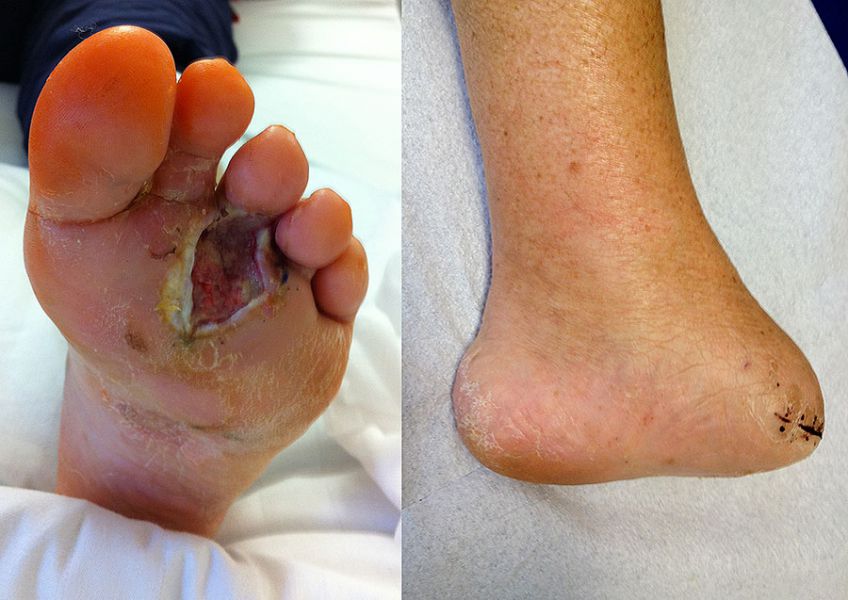

Befund nach R1-Resektion eines Rezidivs eines akrolentiginösen malignen Melanoms mit plantarer Defektwunde (links) und postoperativer Zustand nach Lisfranc-Amputation (rechts).

Abbildung 35

Das Klarzellsarkom ist ein äußerst seltener maligner Weich­teiltumor (1% aller Weichteilsarkome), zeigt aber eine besondere Prädilektion für den Fuß und eine erhebliche Aggressivität. Bis zu 50% aller Klarzellsarkome finden sich hier 5152. Typisch ist eine tiefe, aponeurosen- und sehnennahe Lokalisation. Der Begriff „malignes Melanom der Weichteile“ wird aufgrund der histologischen Ähnlichkeit häufig synonym verwendet. Tatsächlich handelt es sich jedoch um separate klinisch-pathologisch Entitäten, deren Unter­scheidung dem Pathologen nur molekularbiologisch, nicht aber immunhistochemisch möglich ist 51. Die Tumorgröße bei Erstdiagnose ist für das Klarzellsarkom wie auch für andere Weichteilsarkome der wesentliche prädiktive Wert der Prognose. Adjuvante Therapien sind wenig erfolgversprechend und so bleibt die weite Resektion die Therapie der Wahl 53.

Das klassische, kutane Melanom zeigt ebenfalls eine Prädilektion für den Fuß. Bei Frauen finden sich 42% aller malignen Melanome im Bereich der unteren Extremität. Ein Subtyp des kutanen Melanoms, das akrolentiginöse Melanom, weist eine besondere Vorliebe für den palmo-plantaren und subungualen Bereich sowie ein facettenreiches klinisches Bild auf 54 (Abb. 35). Dies unterstreicht die Notwendigkeit der genauen Inspektion im Rahmen der körperlichen Untersuchung. Eine zusätzliche dermatologische Abklärung sollte großzügig indiziert werden. Besondere Beachtung gilt bei beiden Entitäten dem sog. Sentinel-Lymphknoten, welcher bei Lokalisation eines Klarzellsarkoms oder malignen Melanoms der unteren Extremität in den Lymphabflusswegen der ipsilateralen Leiste entnommen wird und erhebliche prognostische Bedeutung besitzt 55.